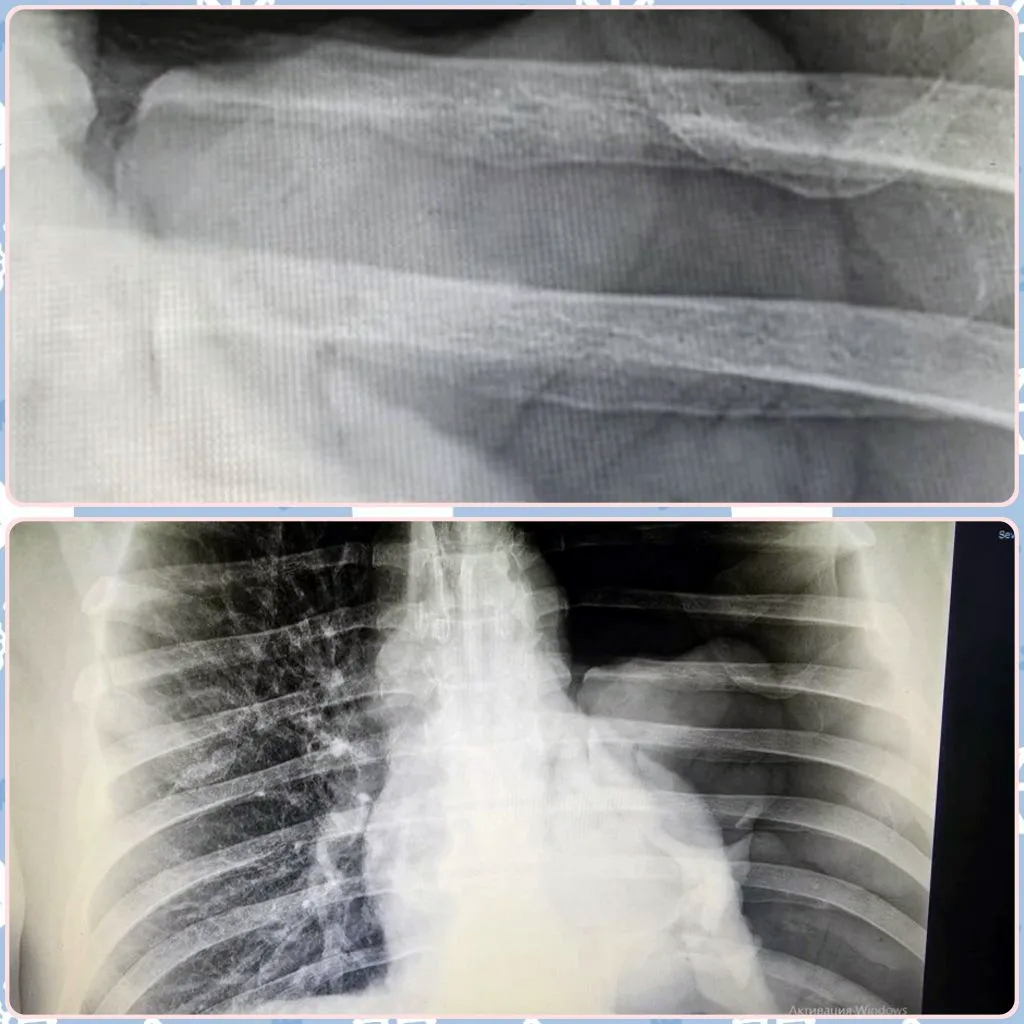

Скрытая угроза: коллапс легкого

49-летний пациент из Маянги упал с двухметровой высоты, но в больницу поехал только через трое суток, когда боль и одышка стали невыносимыми. Диагноз – напряженный тотальный пневмоторакс. Левое легкое полностью коллабировало (сдулось), а плевральная полость заполнилась воздухом, сдавив сердце и сосуды. Хирурги-травматологи экстренно установили дренаж по Бюлау, буквально откачав воздух из грудной клетки. Пациент спасен, но врачи предупреждают: промедление с обращением при такой травме гарантированно ведет к летальному исходу.

Бытовая цена неосторожности

65-летний мужчина решил помыть окна и упал со стремянки. Итог – тяжелый открытый многооскольчатый перелом обеих костей голени со смещением и обширной рваной раной. Врачам пришлось собирать ногу по кусочкам, стабилизируя кости аппаратом внешней фиксации. Теперь пациента ждет этапное лечение и полная неподвижность конечности на срок от 6 до 8 месяцев. Обычная уборка обернулась длительной инвалидностью.